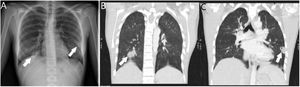

In the Gram stain, 10–25 leukocytes/field were observed in the absence of microorganisms. Samples were inoculated in Thioglycollate® enrichment broth, as well as on different agars (chocolate, CNA and TSA with 5% sheep blood, MacConkey, Sabouraud with chloramphenicol, Brucella, BBE with amikacin and kanamycin-vancomycin blood). After 96 h of incubation, no growth was observed in the cultures. In follow-up CT scans, an involution of the pulmonary septic emboli was observed (Fig. 3), as well as disappearance of the pubic collection.

Clinical courseGiven the patient's improved condition, a peripherally inserted central catheter was placed and antibiotic therapy was changed to intravenous ertapenem 1 g/24 h for 20 days. At discharge, the patient also received metronidazole 500 mg/8 h orally for 10 days, completing four weeks of treatment. After no growth was observed in the cultures, the purulent sample was processed and sequencing of the 16S rRNA gene was performed, obtaining a 435-bp sequence in which Fusobacterium necrophorum (F. necrophorum) was identified, with a homology percentage of 98.65% after introducing it into BLAST®, and it was registered in GenBank® with access number “OP458797” (Appendix A. Supplementary data). It was concluded that the clinical signs and symptoms were consistent with Lemierre syndrome with septic emboli in both lungs and in the pubic symphysis complicated by osteomyelitis and abscessification.